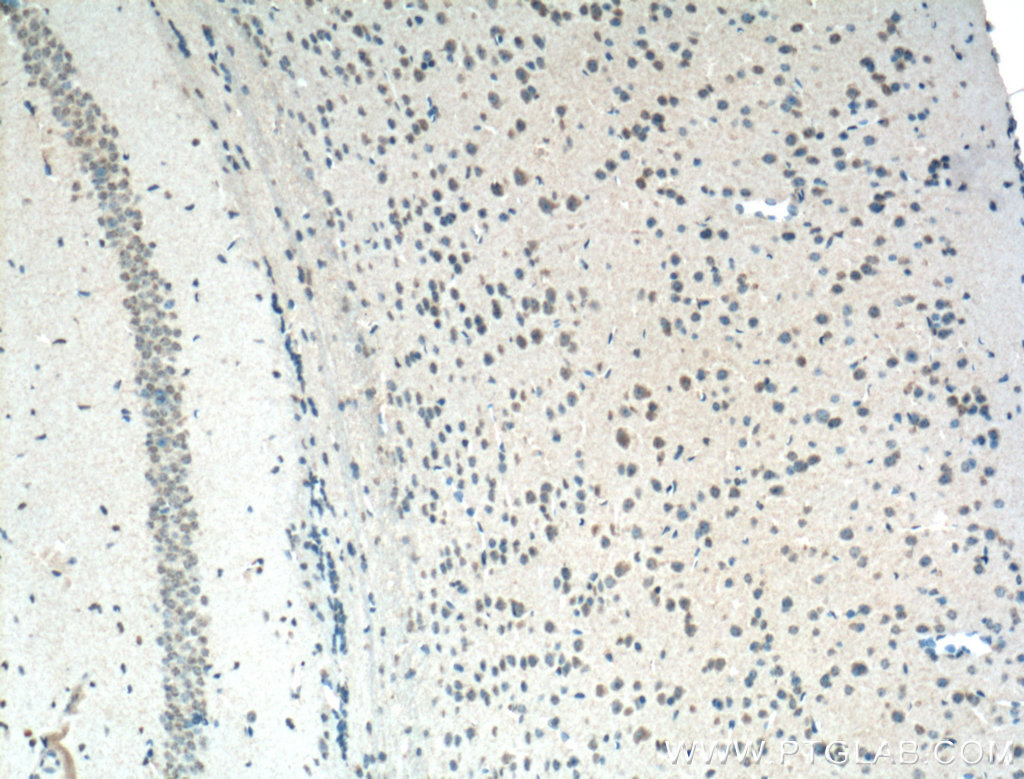

| Positive IHC detected in | human placenta tissue, human prostate cancer tissue, human skeletal muscle tissue, mouse brain tissue, mouse lung tissue Note: suggested antigen retrieval with TE buffer pH 9.0; (*) Alternatively, antigen retrieval may be performed with citrate buffer pH 6.0 |

| Immunohistochemistry (IHC) | IHC : 1:1000-1:4000 |